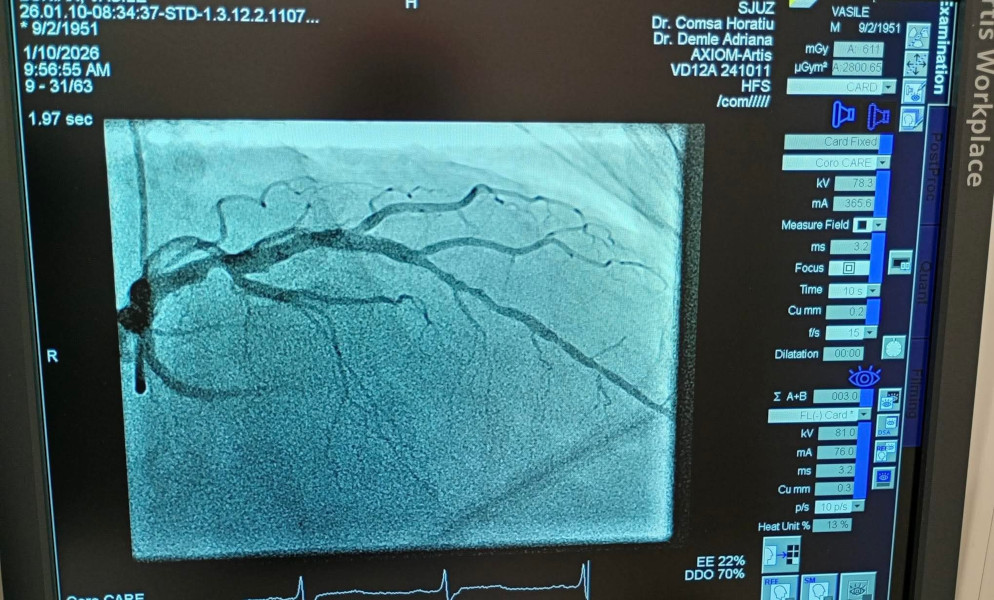

După debutul programului de implantare a stimulatoarelor cardiace în cadrul Compartimentului de Cardiologie Intervențională, astăzi bifăm o reușită istorică: primele 5 angiografii coronariene cu intervenții PCI și montare de stent efectuate cu succes la SJUZ.

Aceste proceduri cu rol diagnostic și terapeutic permit ca pacienții cu afecțiuni vasculare coronariene să fie investigați și tratați local, la Zalău, fără a mai fi necesar transferul către alte centre medicale.